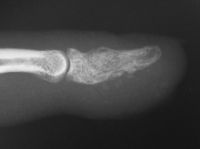

| Case 2. This patient presented months after having "injured" her middle fingertip, feeling that the finger was not normal. Xrays were consistent with an enchondroma and probable dorsal angulation from a healed pathologic fracture. |

| This was excised through a midline palmar incision. The cavity was debrided with a high speed burr, then packed with cancellous bone. |

| Final result. |